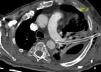

Varón de 63 años, esplenectomizado y sin vacuna antineumocócica. Ingresa con neumonía izquierda y derrame paraneumónico (empiema). Durante colocación de tubo de drenaje pleural (TDP) se aprecia sangrado profuso, pinzándose el mismo. En TAC de tórax (figs. 1 y 2) se objetiva TDP en pared posterior de arteria pulmonar izquierda sin sangrado activo. Mediante toracotomía se observa TDP que perfora parénquima pulmonar hasta introducirse en pared posterior de arteria pulmonar, identificándose sangrado arterial tras la movilización cuidadosa del TDP. Se consigue hemostasia tras realización de bolsa de tabaco que engloba la entrada arterial del TDP. El postoperatorio transcurrió sin complicaciones.